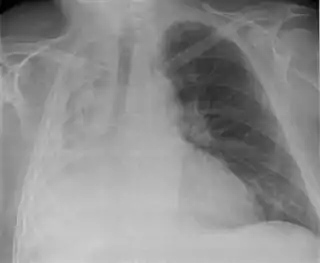

![]() Atelectasia completa del pulmón derecho | ||

- Radiografía del tórax: Detecta los siguientes signos radiológicos:

Signos Directos:

- Retracción de las cisuras lobares.

- Radiopacidad homogénea del lado de la lesión.

- Acercamiento broncovascular.

Signos Indirectos:

- Retracción del Mediastino hacia el lado de la lesión.

- Elevación del hemidiafragma.

- Disminución de los espacios intercostales.

- Enfisema compensador( Hiperinsunflación).

- Desplazamiento del hilio hacia el lado de la lesión.

- Aproximación de las costillas.

En el adulto previamente sano que presente una atelectasia hay que sospechar una neoplasia que obstruye el bronquio. La presencia de todos los signos directos más la mayoría o todos los indirectos confirman la atelectasia.